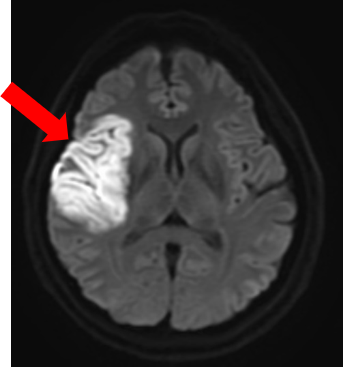

●脳流血シンチグラフィ

脳流血シンチグラフィは、脳にある血管の血流量を調べる検査です。脳流血を反映する薬剤を投与し、脳血流が豊富なところを赤色で、血流が乏しくなっているところを青色で表示して画像化します。

下に提示した症例は、脳梗塞を発症した患者さんの、核医学とMRI画像です。左図の脳血流シンチグラフィ画像では、画像左側が緑や青色で表示され、脳血流が低下していることが分かります。中央の画像では、脳血流が低下しているところが白く描出され、右図の脳血管を描出したMRI画像では左の脳動脈は描出(青矢印)されていますが、右の脳動脈は描出されていません(赤丸)。